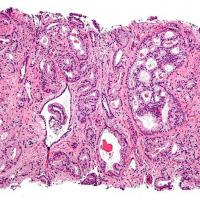

La terapia “chemio-free”, con l'aggiunta della molecola abiraterone al trattamento ormonale standard, si conferma efficace nel mantenere stabile la malattia, e quindi allungare la sopravvivenza dei pazienti con tumore alla prostata metastatico alla diagnosi e ad alto rischio, con più del 50% dei pazienti ancora in vita a quarantuno mesi di follow-... Continua